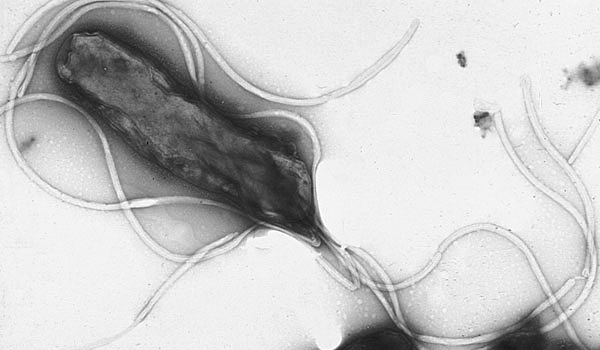

Escherichia Coli (E.coli) este o bacterie care se găseşte de obicei în intestinele oamenilor, dar şi la animalele cu sânge cald.

Cele mai multe tulpini ale acestei bacterii sunt inofensive. Există, totuşi, unele tulpini, precum cel al „enterohemoragiei E.coli” (EHEC), care pot provoca toxiinfecţii alimentare severe.